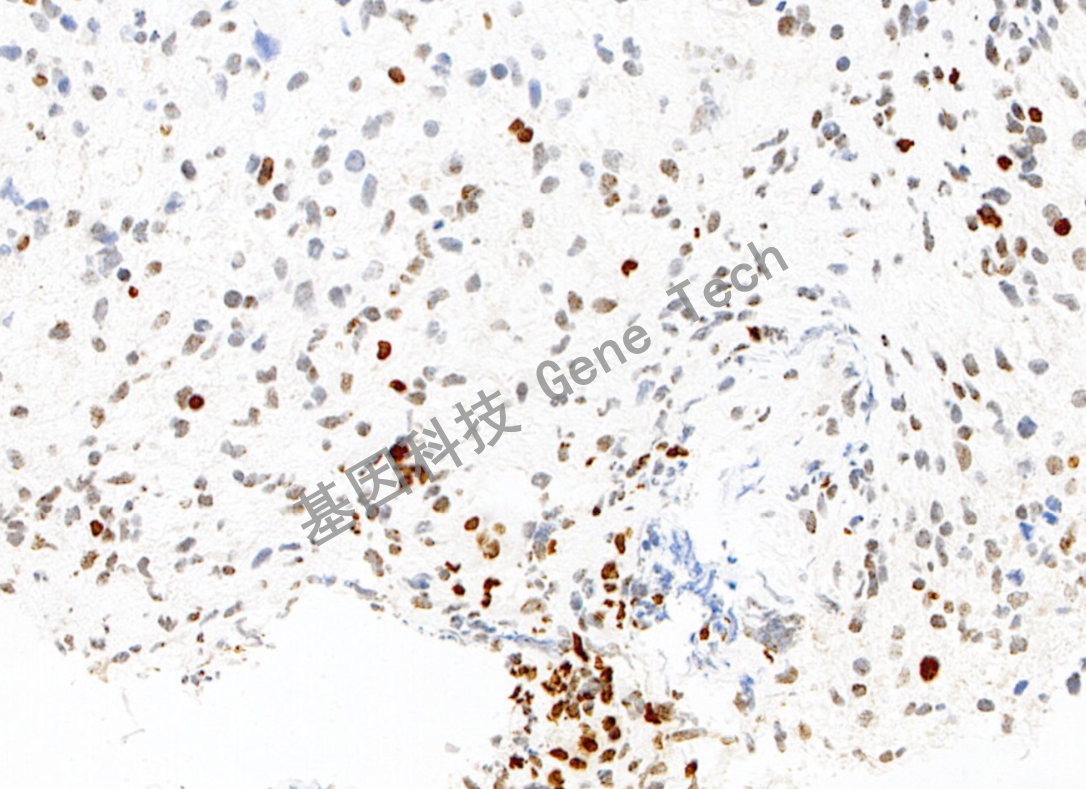

高级别胶质瘤石蜡切片,用 H3K27Me3(GT2368)染色,细胞核阳性,DAB 显色。